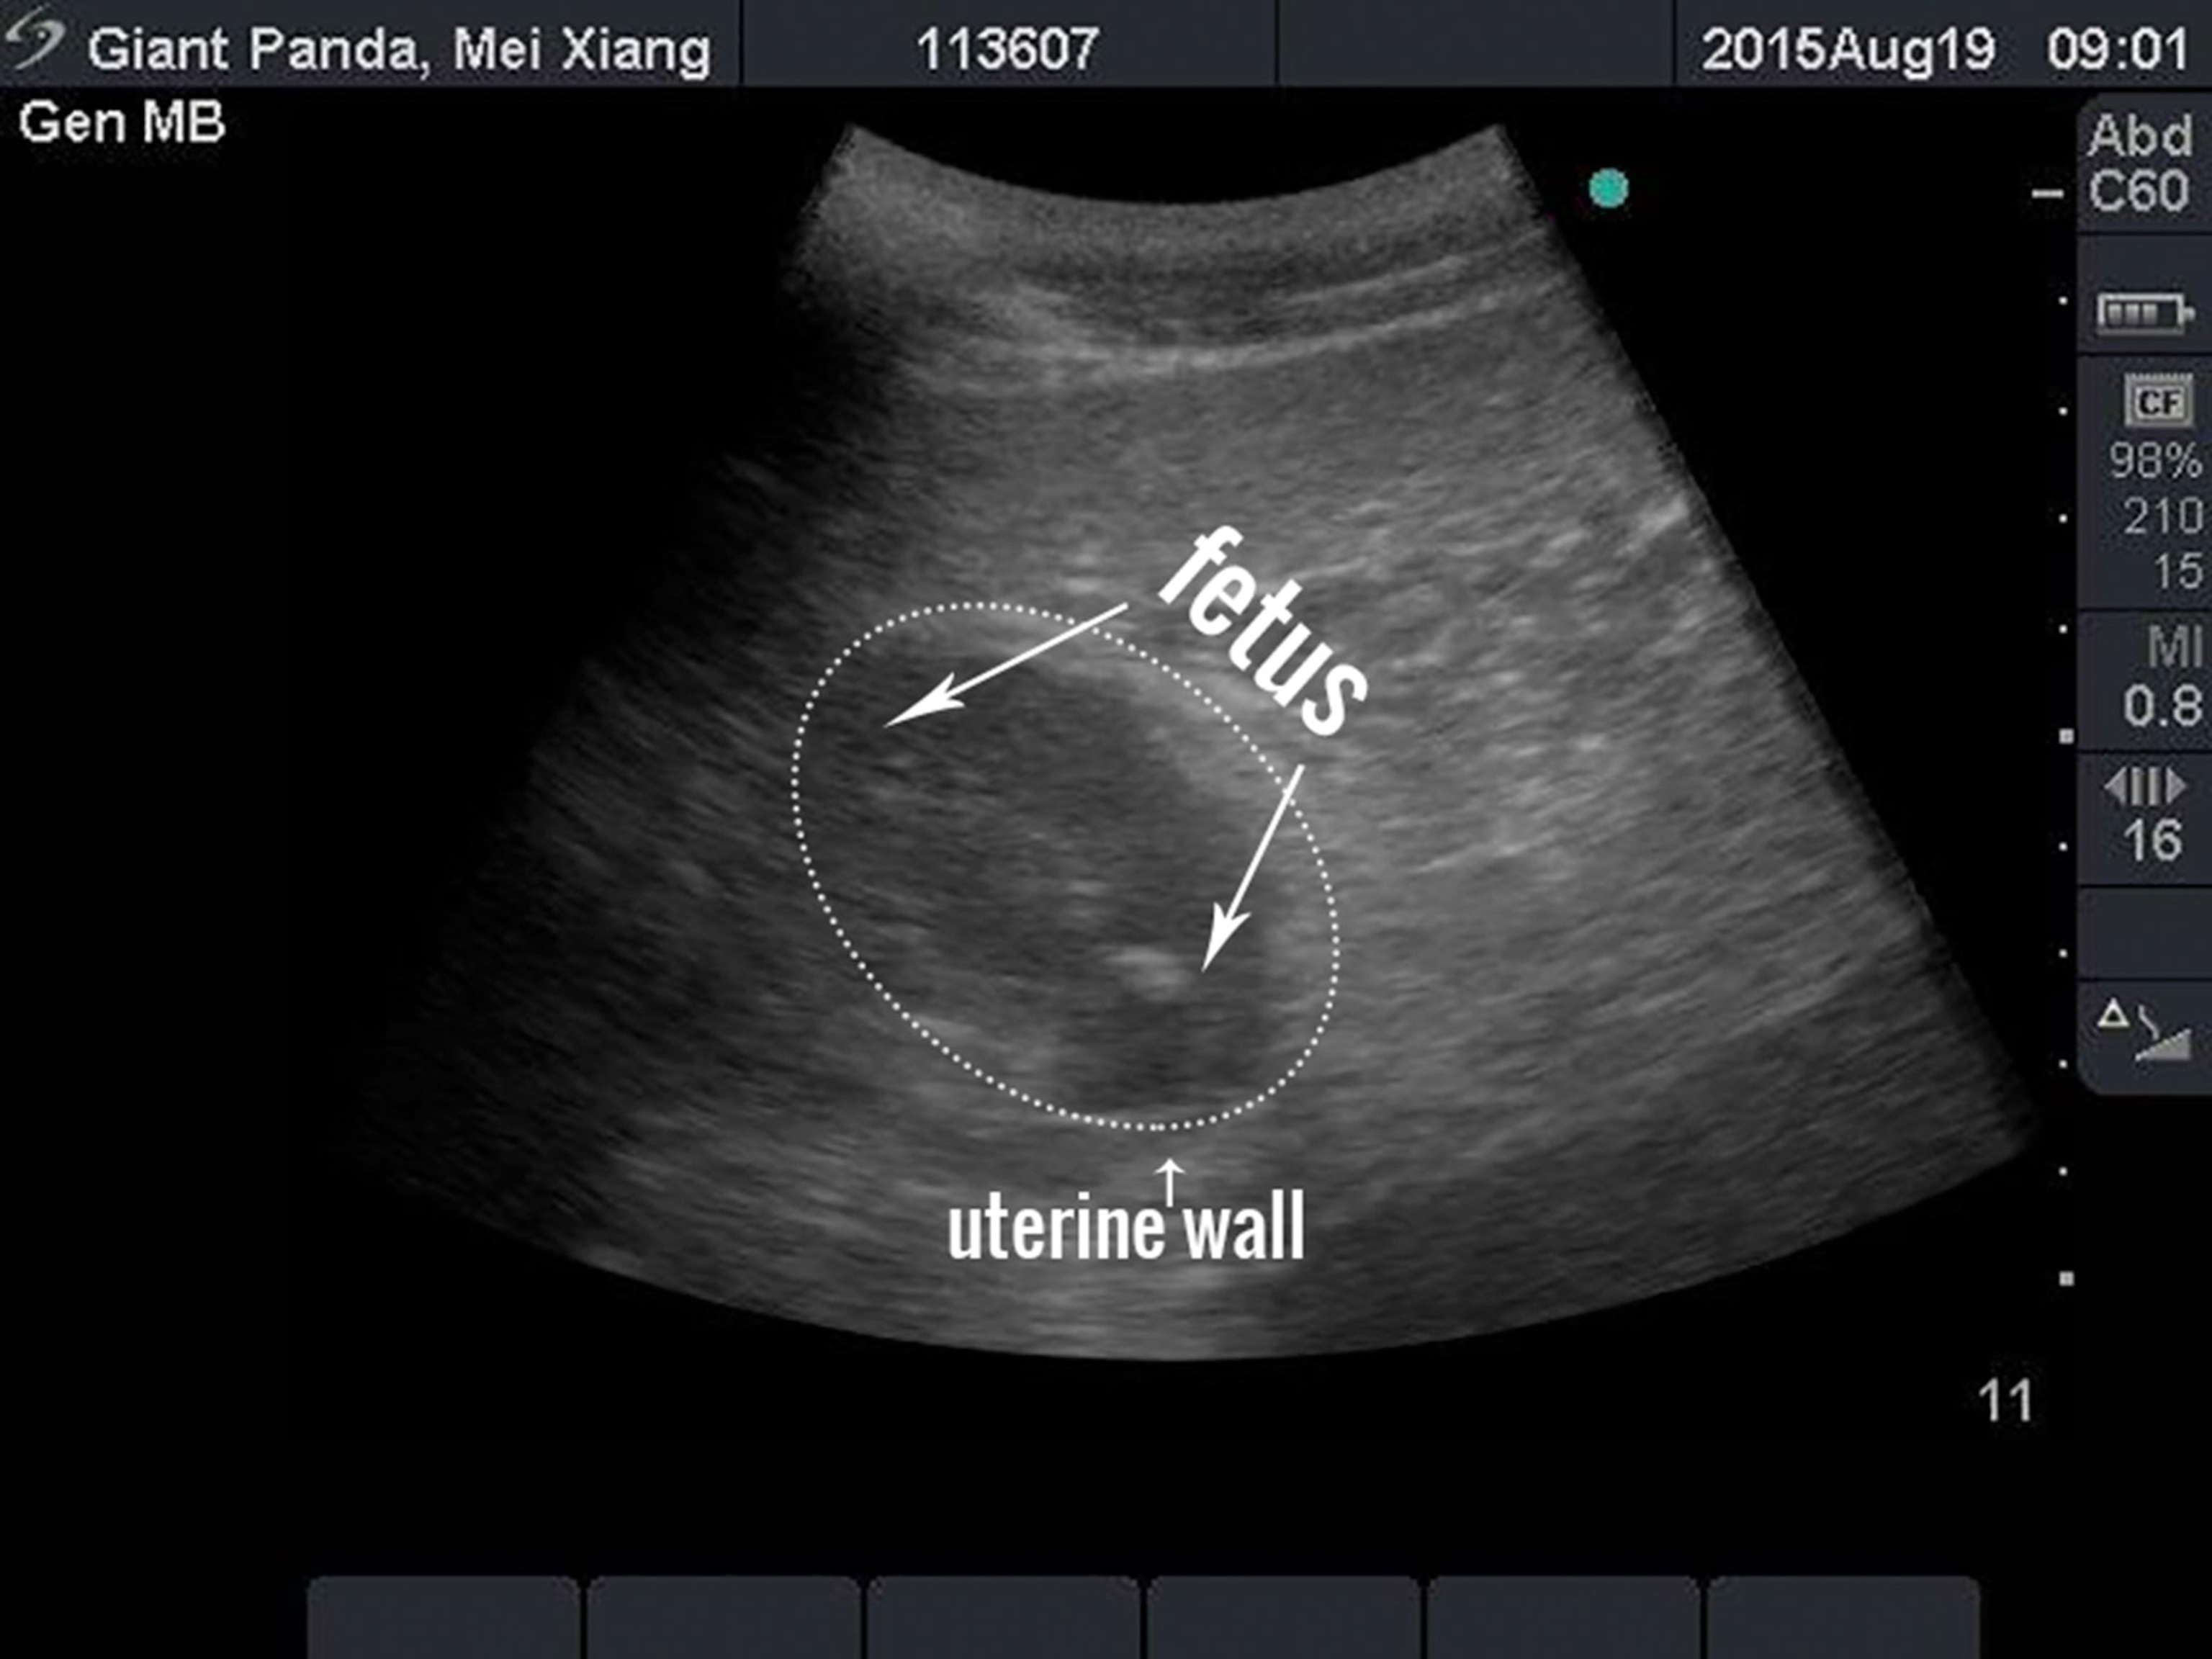

The Smithsonian National Zoo has detected a possible fetus in an ultrasound of its giant panda, Mei Xiang. This is a first for the zoo’s panda breeding efforts.

The discovery of what veterinarians think is a 1.5 inch (4-centimeter) long fetus means Mei could give birth as early as next week, according to a statement released after the August 19 ultrasound.

An ultrasound only shows a panda fetus within the last 20 days of a pregnancy, and even then, "it’s just not easy to hit a moving target with the ultrasound probe," Neiffer says. "Thank you, Mei Xiang!"

A panda fetus is extremely slow-growing, making it hard to detect pregnancy.

Giant pandas undergo what's called "delayed implantation," which means that once the egg is fertilized, everything gets puts on hold. The future fetus "virtually stops growing in the uterus and instead free-floats without growth until the time is right for it to implant in the uterine wall," the San Diego Zoo’s blog explains.

That's usually within the last weeks of gestation, so zoo veterinarians often don't know if a panda is pregnant until the little girl or guy pops out.

However, ultrasound technology has improved in recent years, Sutherland-Smith noted, and her team has been able to both detect pregnancies and predict roughly when Bai Yun will give birth.